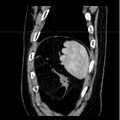

Fig. 9b is a schematic diagram of the second binarized image viewed from the sagittal plane direction.

Fig. 9c is a schematic view of the second binarized image as viewed from the coronal plane direction.

fig. 8a-8c are raw three-dimensional data of sequential CT images viewed from three directions, the transverse, sagittal and coronal planes, respectively. Fig. 9a to 9c are the second binarized images obtained after the method removes the bed plate area, respectively, and it can be seen from fig. 9a to 9c that none of the skin surface contours of the human body area is damaged. Fig. 10a to 10c are respectively third binarized images obtained after filling the cavity by the method, and it can be seen from fig. 10a to 10c that the third binarized images are completely overlapped with the original three-dimensional data of the sequence CT image, and the lung region with a low threshold value is effectively filled. As can be seen from FIGS. 11a-11d, after another serial CT image is reconstructed by the method, the three-dimensional model of the skin can be fused with the third binary image and the serial CT image. And finally mapping the obtained three-dimensional model of the skin back to a 2D mode, and comparing the coincidence degree of the skin boundary in the three-dimensional model of the skin and the binary image to obtain figures 12a-12 c. In addition, the three-dimensional models of the skin of other parts of the human body obtained by the method are shown in figures 13a-13 c.